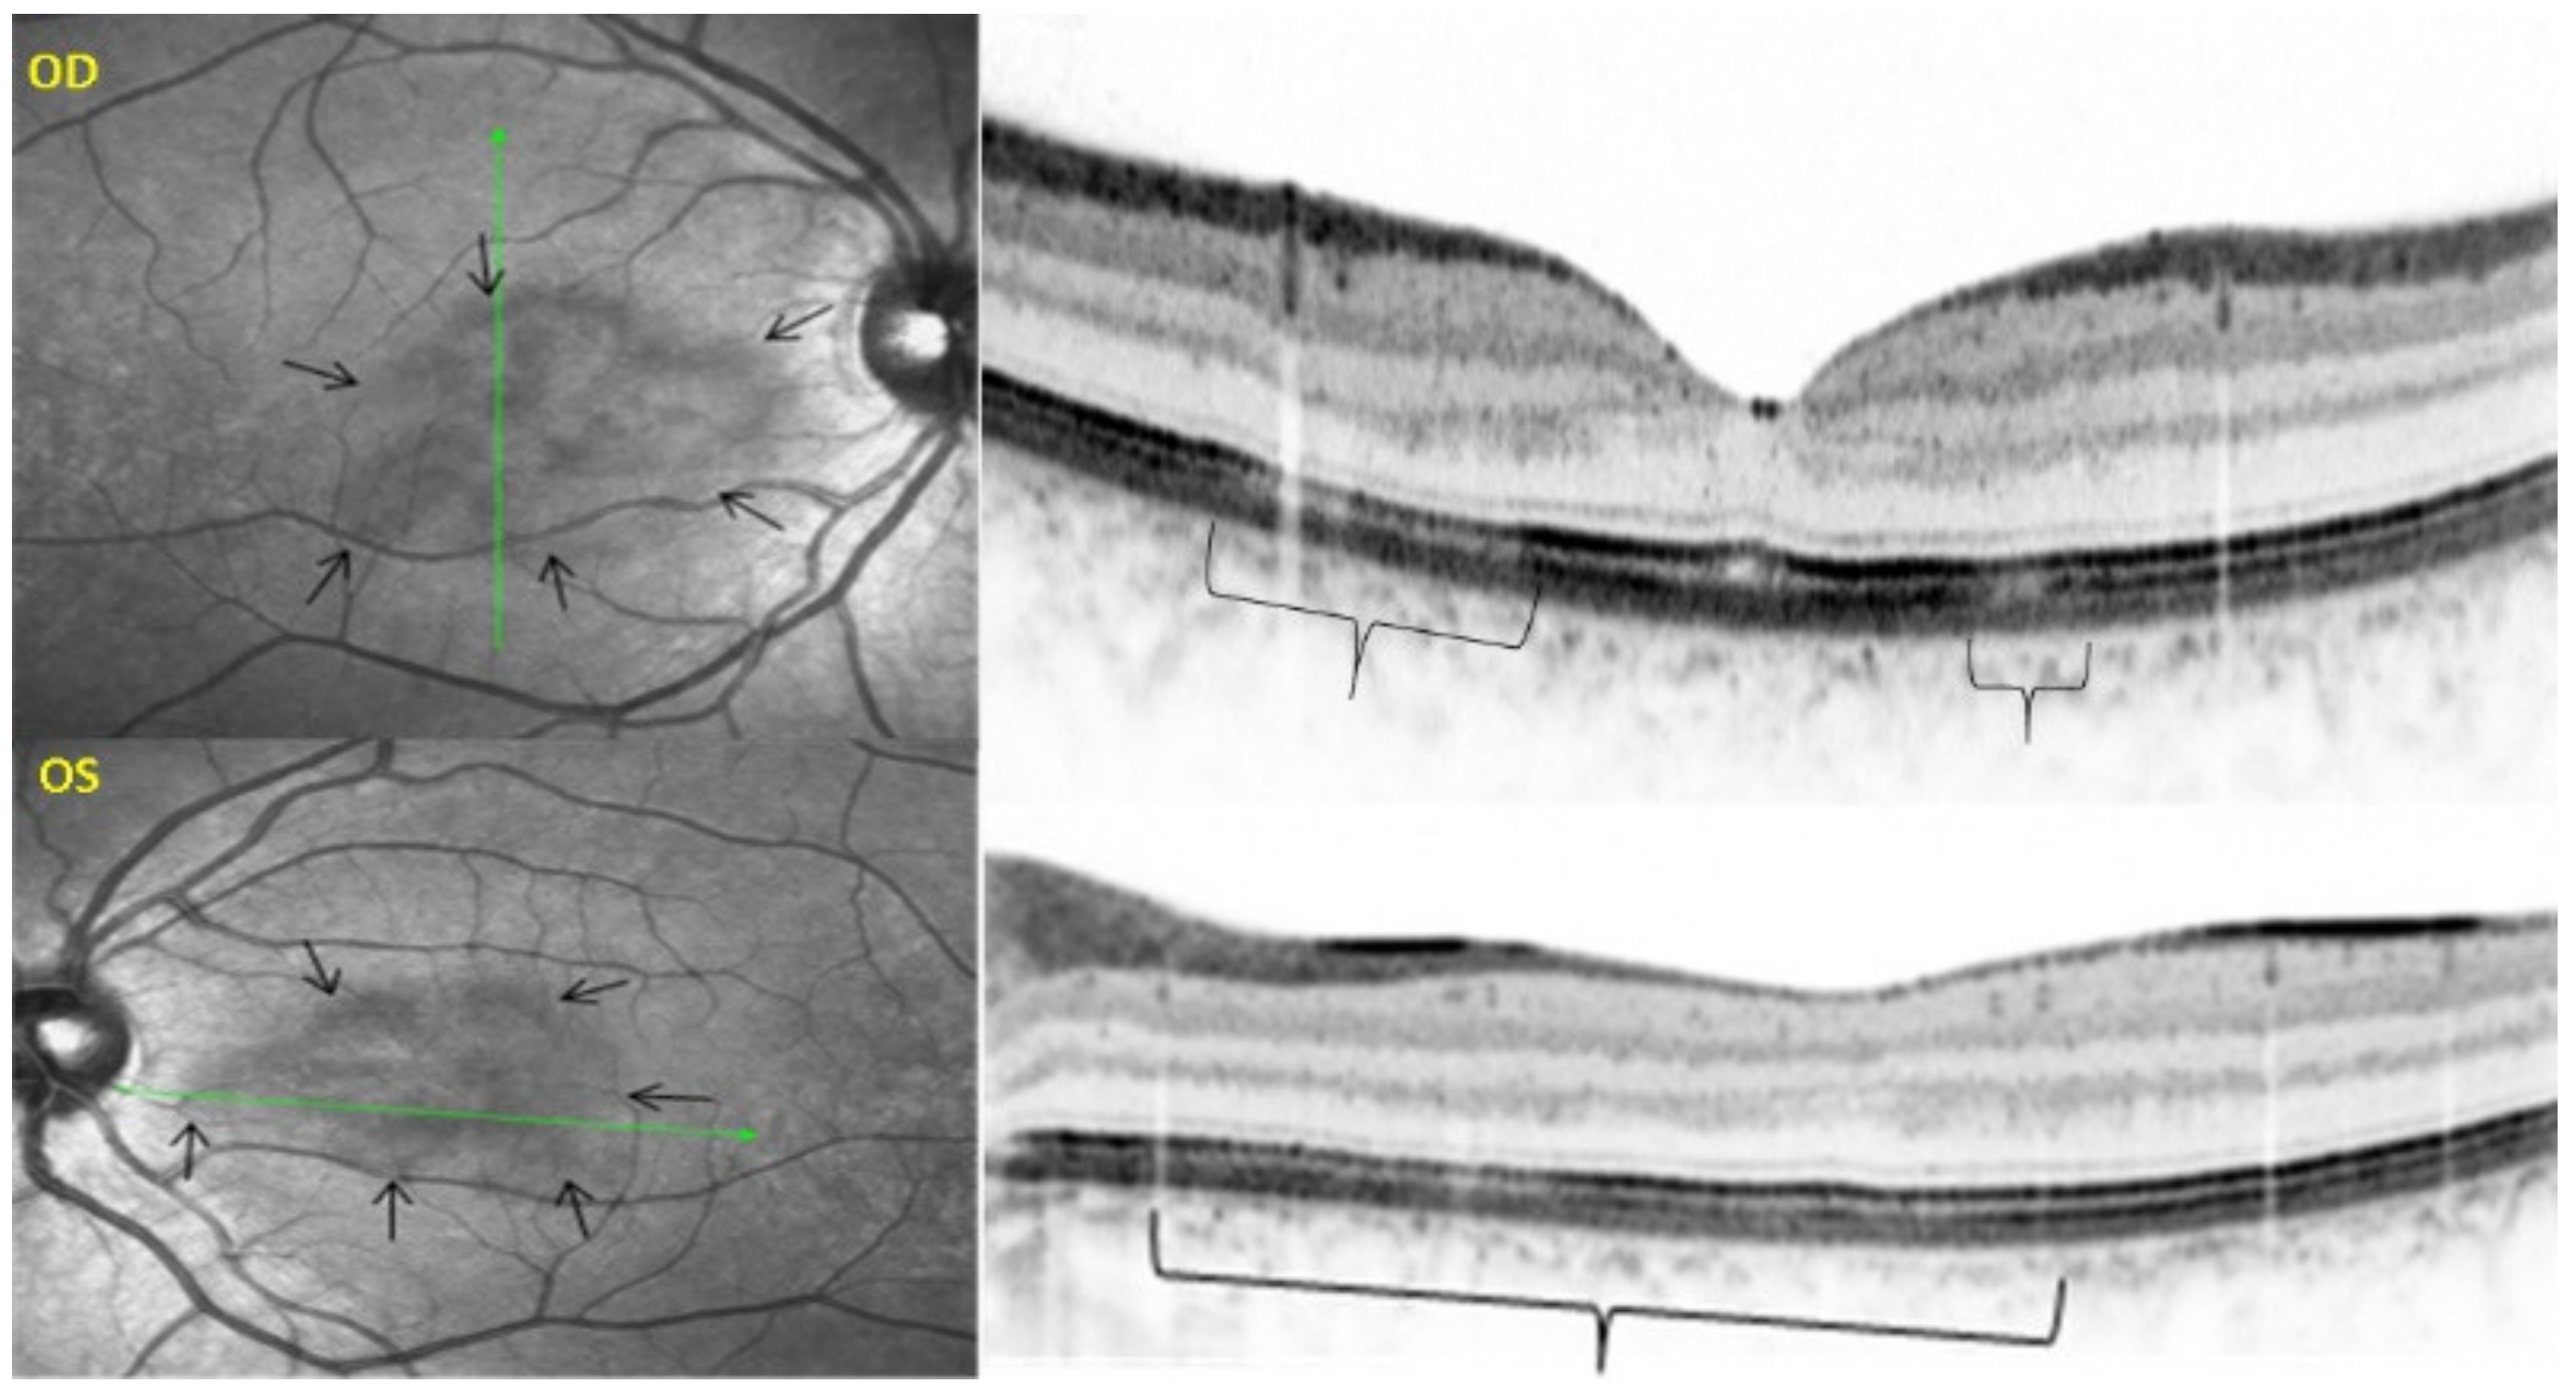

Figure 50.

EDI-OCT measuring choroidal thickness in VKH disease. At presentation (a), mean subfoveolar thickness is increased to 502.6 µm. After introduction of steroidal and non-steroidal immunosuppression (b), thickness was reduced to 334.3 µm.